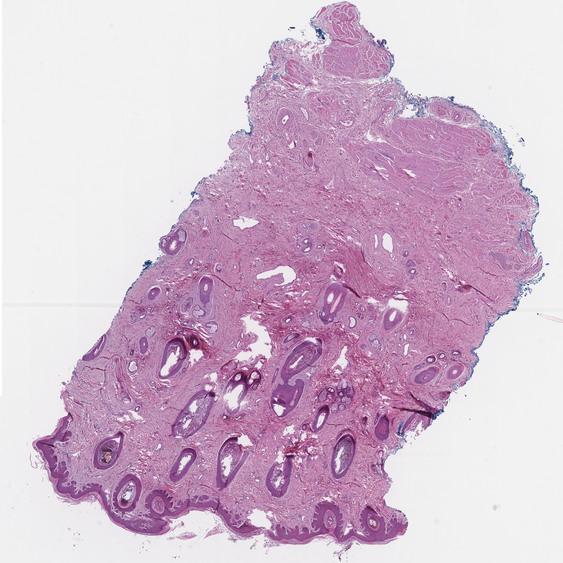

The model results are integrated in the pathologist workflow. The pathologist will receive the information from the model as annotations that are rendered from the generated XML file in a WSI viewer.

Figure 5: A fully annotated whole slide image on the pathologist’s viewer

Refer to caption

Figure 6: Zoomed-in view of an annotated WSI

The pathologists can themselves annotate False Positive and False Negative Examples by adding annotations to their slide viewer. Those feedback annotations get stored in a database that is read out daily. Based on the feedback information new images for fine tuning of the Detection model (3.4) are created. Fine-tuning is performed on a regular basis, dependent on the feedback volume.